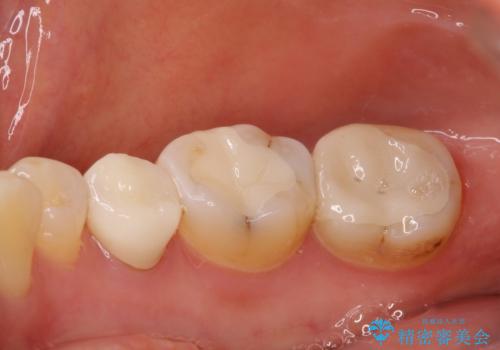

必要な歯に根管治療を行い、オールセラミッククラウンにて補綴治療を行うこととしました。

一部根管治療では症状が改善しなかったため、歯根端切除術を行いました。